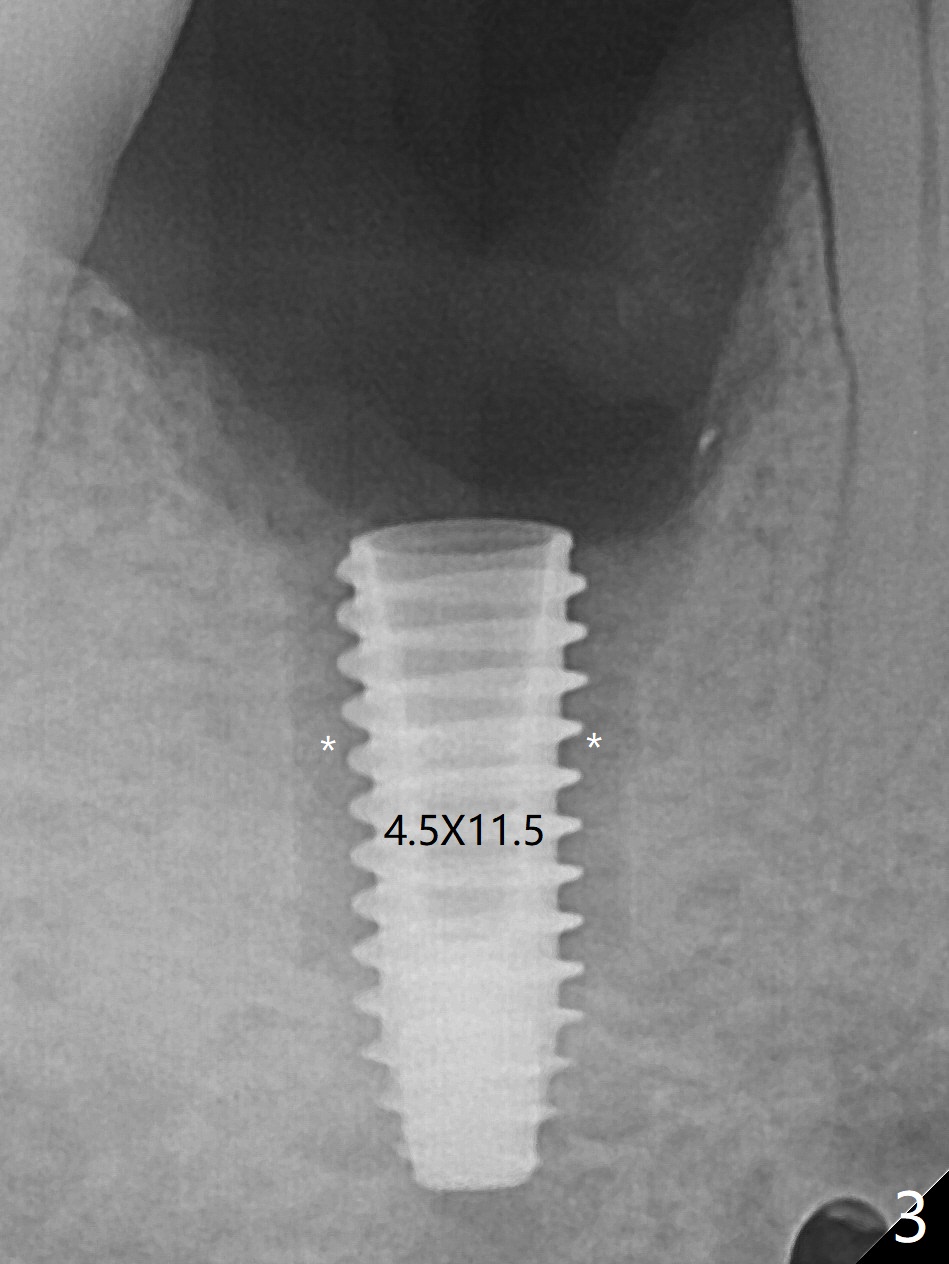

When the woman with periimplantitis at #30 returns to clinic, the abutment is found to be fractured (Fig.1 *) and difficult to remove. After implant removal with trephine burs, osteotomy is initiated lingual (Fig.2). A smaller and shorter implant (4.5x11.5 vs. 5.0x13 mm previously) is placed deeper (Fig.3) so that there is space for sticky bone buccal and coronal (Fig.4 *, 5 (postop reanalysis of preop CT)). After placement of 2 pieces of PRF membranes, the wound is closed with 4/0 PGA. The buccal flap is perforated due to periimplantitis and surgical manipulation. Periodontal dressing is applied.